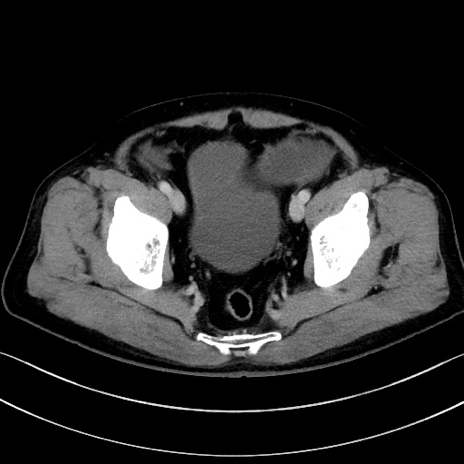

症例15(横断像)

【症例】70歳代男性

【主訴】腹痛

【現病歴】今朝から腹痛あり。全体的に痛い。特に左上の方。排ガスが今日はない。冷や汗が出る。

【既往歴】直腸癌術後

【身体所見】左側腹部〜上腹部に圧痛あり。腹膜刺激症状明らかなではない。軽度反跳痛。左下腹部に術後瘢痕あり。

【データ】WBC 7700、CRP 0.02